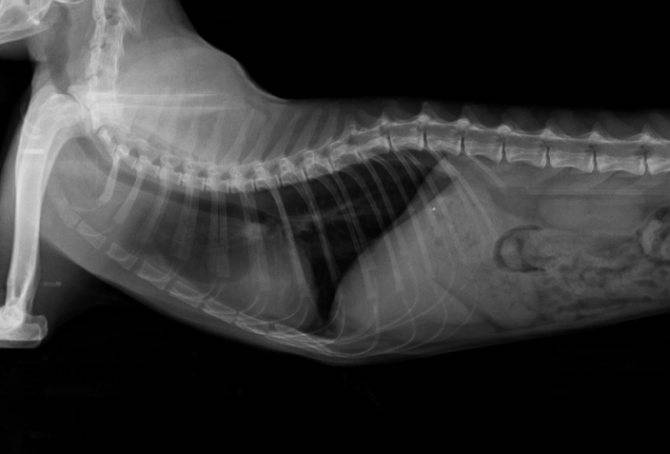

- Лучевая диагностика: КТ, МРТ, рентгенография, УЗИ.

| Медиастинальная форма | Затрудненное дыхание (одышка), кашель, хрипы, скопление жидкости в грудной полости (плевральный выпот), увеличение лимфатических узлов в грудной клетке (видно на рентгене). | Химиотерапия, дренирование плевральной полости для удаления жидкости, кислородная терапия, противовоспалительные препараты. |

Лимфоузлы на шее и груди увеличиваются, кошка тяжело дышит, кашляет, задыхается. Часто она не может глотать, тогда появляется слюнотечение. В плевре накапливается жидкость, появляется выпот. Слизистые оболочки приобретают синюшную окраску. Диагностируются шумы в сердце. Опухоль затрагивает средостение, вилочковую железу и близко расположенные лимфоузлы. Анализ крови показывает повышенный уровень кальция. Медиастинальной форме лимфомы почти всегда сопутствует лейкоз.